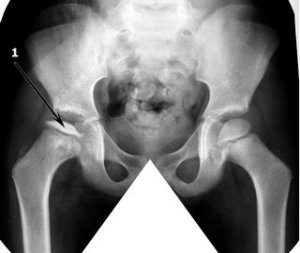

Болезнь Пертеса, которая носит полное название Пертеса-Легга-Кальве – это остеохондропатия головки бедренной кости, которая вызывается некрозом без присутствия инфекции. Заболевание протекает в области тазобедренного сустава и его головки. Чаще всего оно выявляется у детей или у подростков, а в дальнейшем приводит к развитию деформирующего артроза.

Болезнь Пертеса-Легга-Кальве – это асептический некроз. То есть,в этом случае воспаление в области сустава появляется без участия каких-то микробов и гноя. Отмирание костной ткани происходит в области головки кости, на поверхности.

Заболевание начинается с синовита. Если недуг будет диагностирован в этом случае, то его развитие можно затормозить. После этого синовит сменяется некрозом. В зависимости от того, какое время длится воспаление, будет разной и интенсивность его поражения. Здесь будут затрагиваться костный мозг, хрящи, и даже шейка бедра. Болезнь имеет несколько стадий.

На первой стадии выявляется только некроз головки бедра. Во время второй стадии может появиться перелом. На третьей стадии происходит рассасывание отмерших тканей, при этом наблюдается укорочение ноги. Потом начинается разрастание соединительной ткани и, наконец, происходит срастание кости за счёт кальция и образование новой костной ткани.